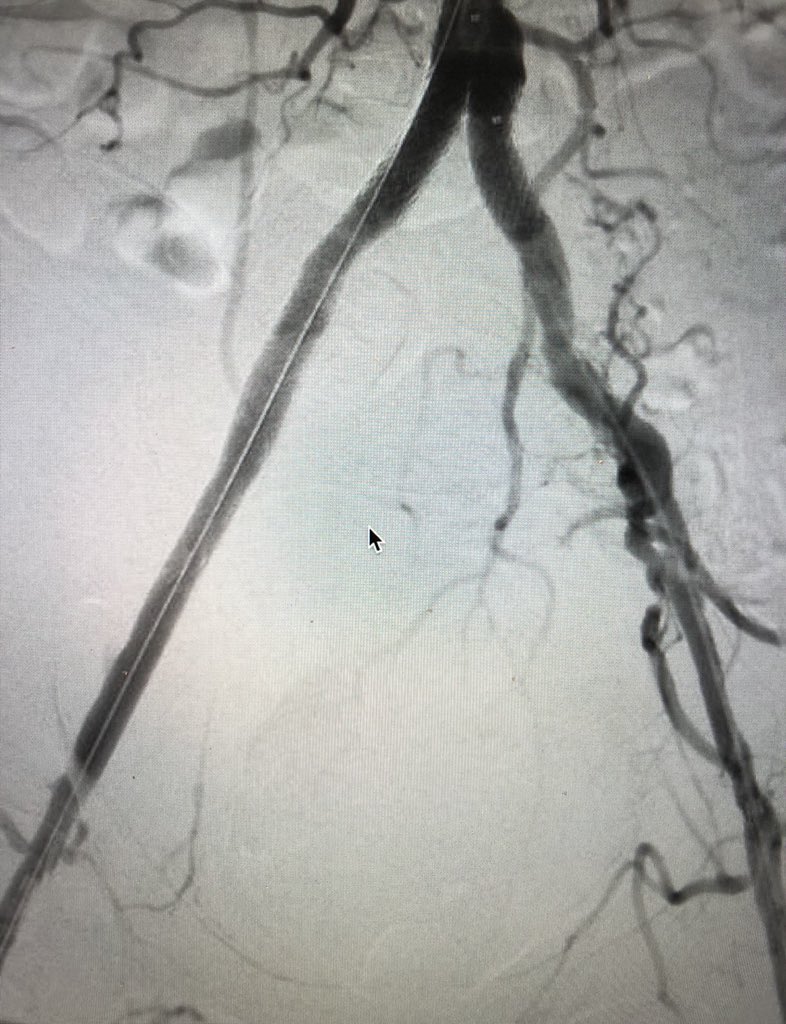

MRA can be MORE sensitive to tibial occlusive disease than DSA. MRA helped plan approach due to knowledge of hibernating AT and peroneal lumen. Successful antegrade luminal recan for #CLI #CLIfighters #mylegmylife @FadiSaab17 @Mustapja @roblookstein @DrBTKatzen @BOlivieriMD